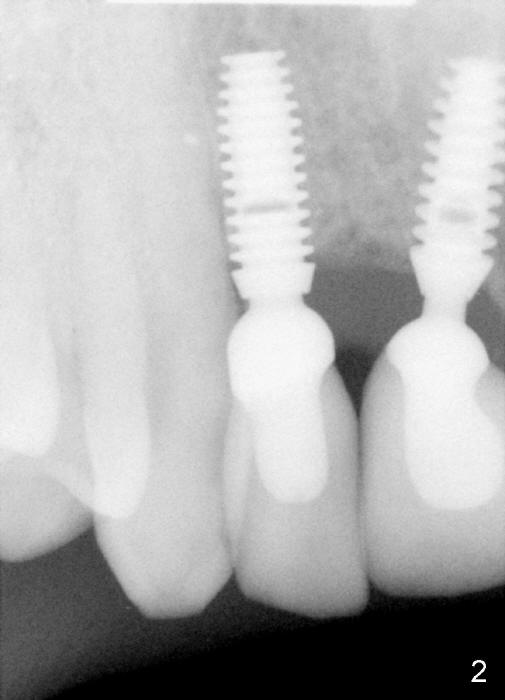

When the IACs were re-tapped in more secure manner by Carmen, the new X-ray reveals something unexpected and interesting (Fig.2).  What do you see?

By the way, why is the image in Fig.1 not as good as that of Fig.2?  How can you get the image of Fig.2 every time?